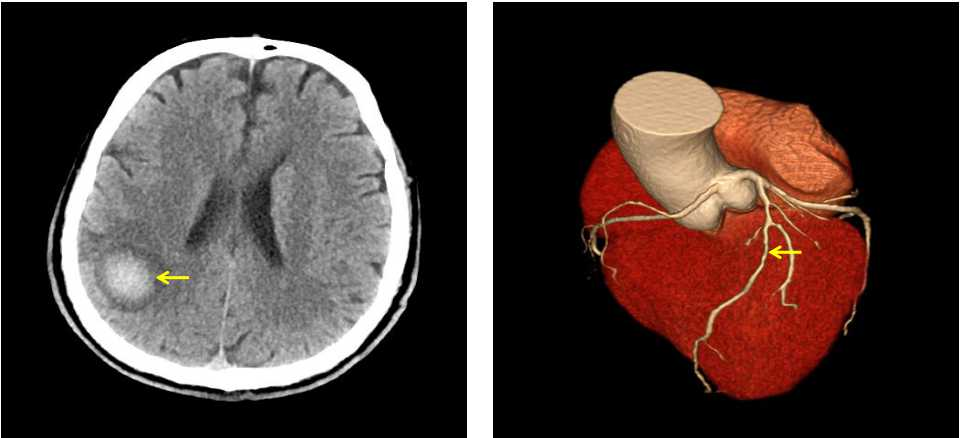

左起:图2a图2b

图2a右侧顶叶脑出血;图2b心脏冠状动脉CTA 前降支狭窄